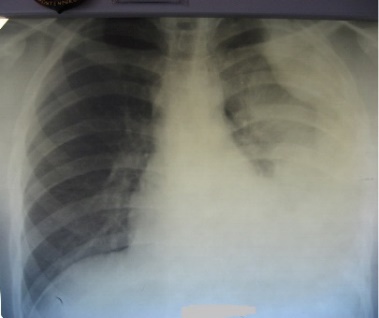

Общее состояние удовлетворительное. Кожные покровы бледные, обычной влажности. Рост 175 см, масса тела 70 кг. ЧДД – 22 в 1 минуту, над правым легким дыхание жёсткое, проводится во все отделы; над средними и нижними отделами левого легкого – резко ослабленное. ЧСС 96 в 1 минуту, тоны сердца приглушены, ритмичные, АД 100/60 мм рт. ст. Живот мягкий, безболезненный, печень не увеличена.

При рентгенологическом исследовании органов грудной клетки выявлены изменения.

После дополнительного обследования диагностирован туберкулез. В плевральной жидкости методом прямой микроскопии мазков КУМ не обнаружены. Определена устойчивость возбудителя заболевания к изониазиду (H) и рифампицину (R).